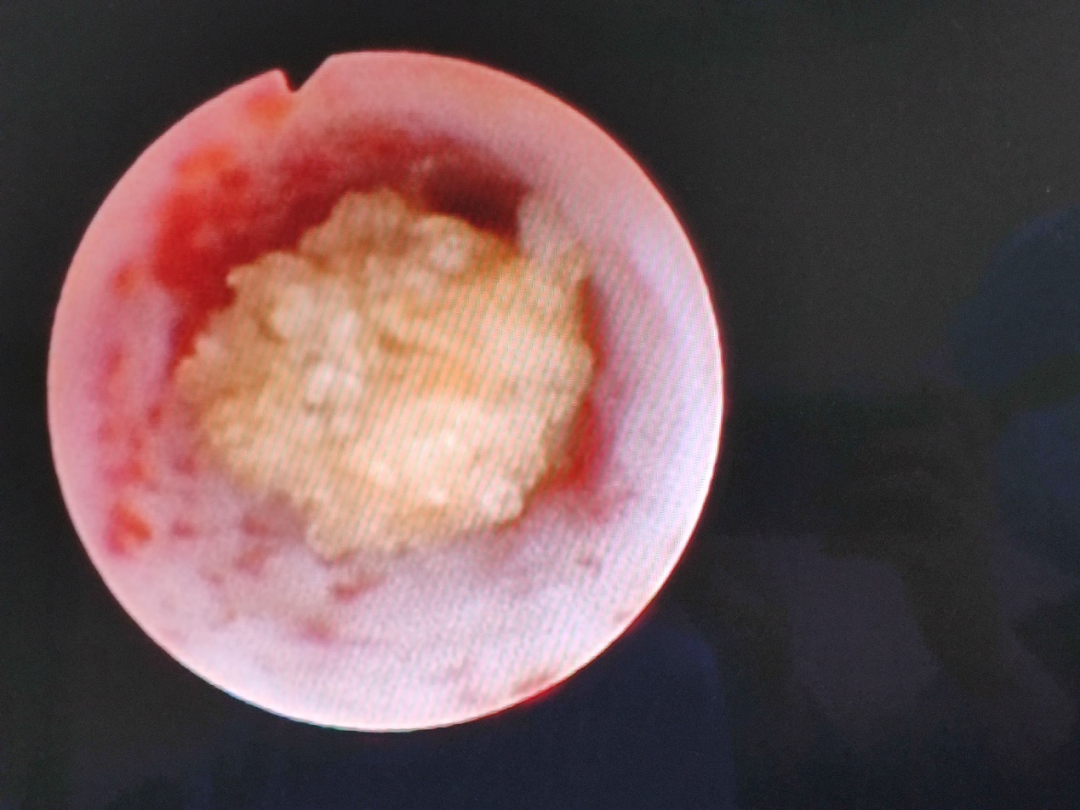

術中,行左側輸尿管鏡探查,見“左側輸尿管結石處管壁毛糙,管腔狹窄,數枚小結石嵌插入粘膜內,幾乎完全堵塞輸尿管。主治醫生先使用鈥激光將其打碎,再用套石網籃將殘石取出,最后放置左側輸尿管支架管。經過一番努力,手術取得圓滿成功。